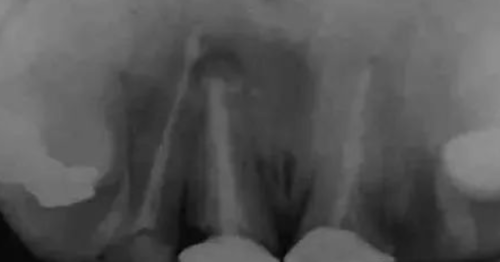

图3:牙根曲度大,但是短小,故而可以认为根部骨阻力小。那就很简单喽。